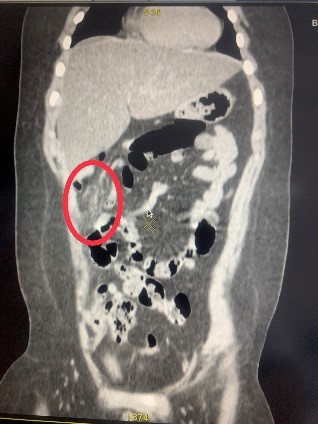

Hình 1,2,3: Hình ảnh theo dõi xoắn mạc nối trên phim chụp CT ổ bụng

khác. Sau đó trẻ được chụp CT ổ bụng để chẩn đoán. Với kết quả ruột thừa bình

thường nhưng có đám viêm nhiễm vùng mạn sườn phải, trẻ đã được các bác sĩ khoa

Ngoại tổng hợp chẩn đoán Xoắn mạc nối lớn và chỉ định mổ cấp cứu bằng phương